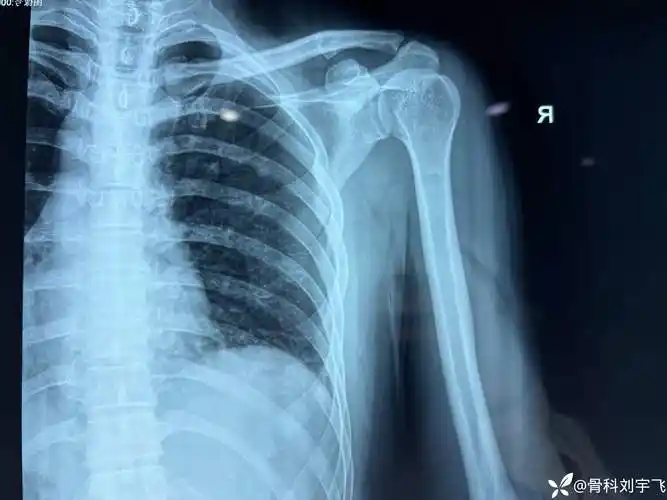

灯泡征高度提示肩关节后脱位